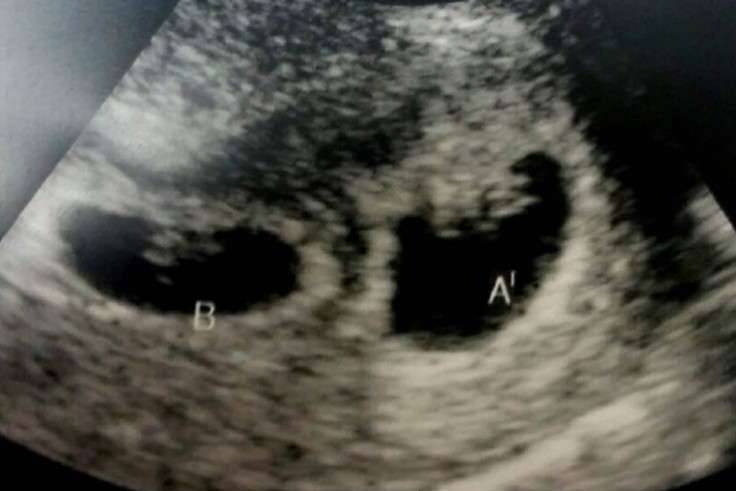

▼经过医生的检查,宣布了一个令夫妻两人完全无法相信的结果,丹妮莎竟又怀上了第3对双胞胎。

▼医生后来发现,原来丹妮莎拥有特别的体质,每一次排卵的时候都会释放出两颗卵子,所以才会每次都轻易地怀上双胞胎。

▼而这样的机率只有1/88000,虽然可能会很辛苦,但是丹妮莎决定不减胎也不堕胎,要将每一个宝宝都生下来。